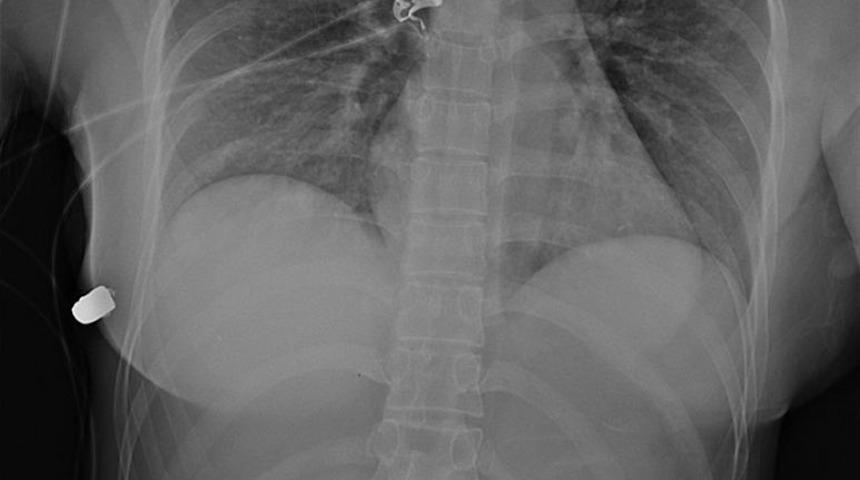

Kadının göğsüne yapılan tomografide sol taraftan giren ve sağ tarafa geçtikten sonra oradaki silikonda asılı kalan bir mermi tespit edildi. Olay hakkında soruşturma yapan polis, mermiyi ateşleyen silah ve kişiyi tespit edemedi.

Doktorlar raporda, silikon üzerindeki izleri inceleyerek silikonun büyük bir ihtimalle kadının hayatını kurtardığı sonucuna vardı. Rapora göre vücuda sol taraftan vücuda giren mermi, kalbe doğru ilerleyebilecekken silikon sayesinde yön değiştirdi.